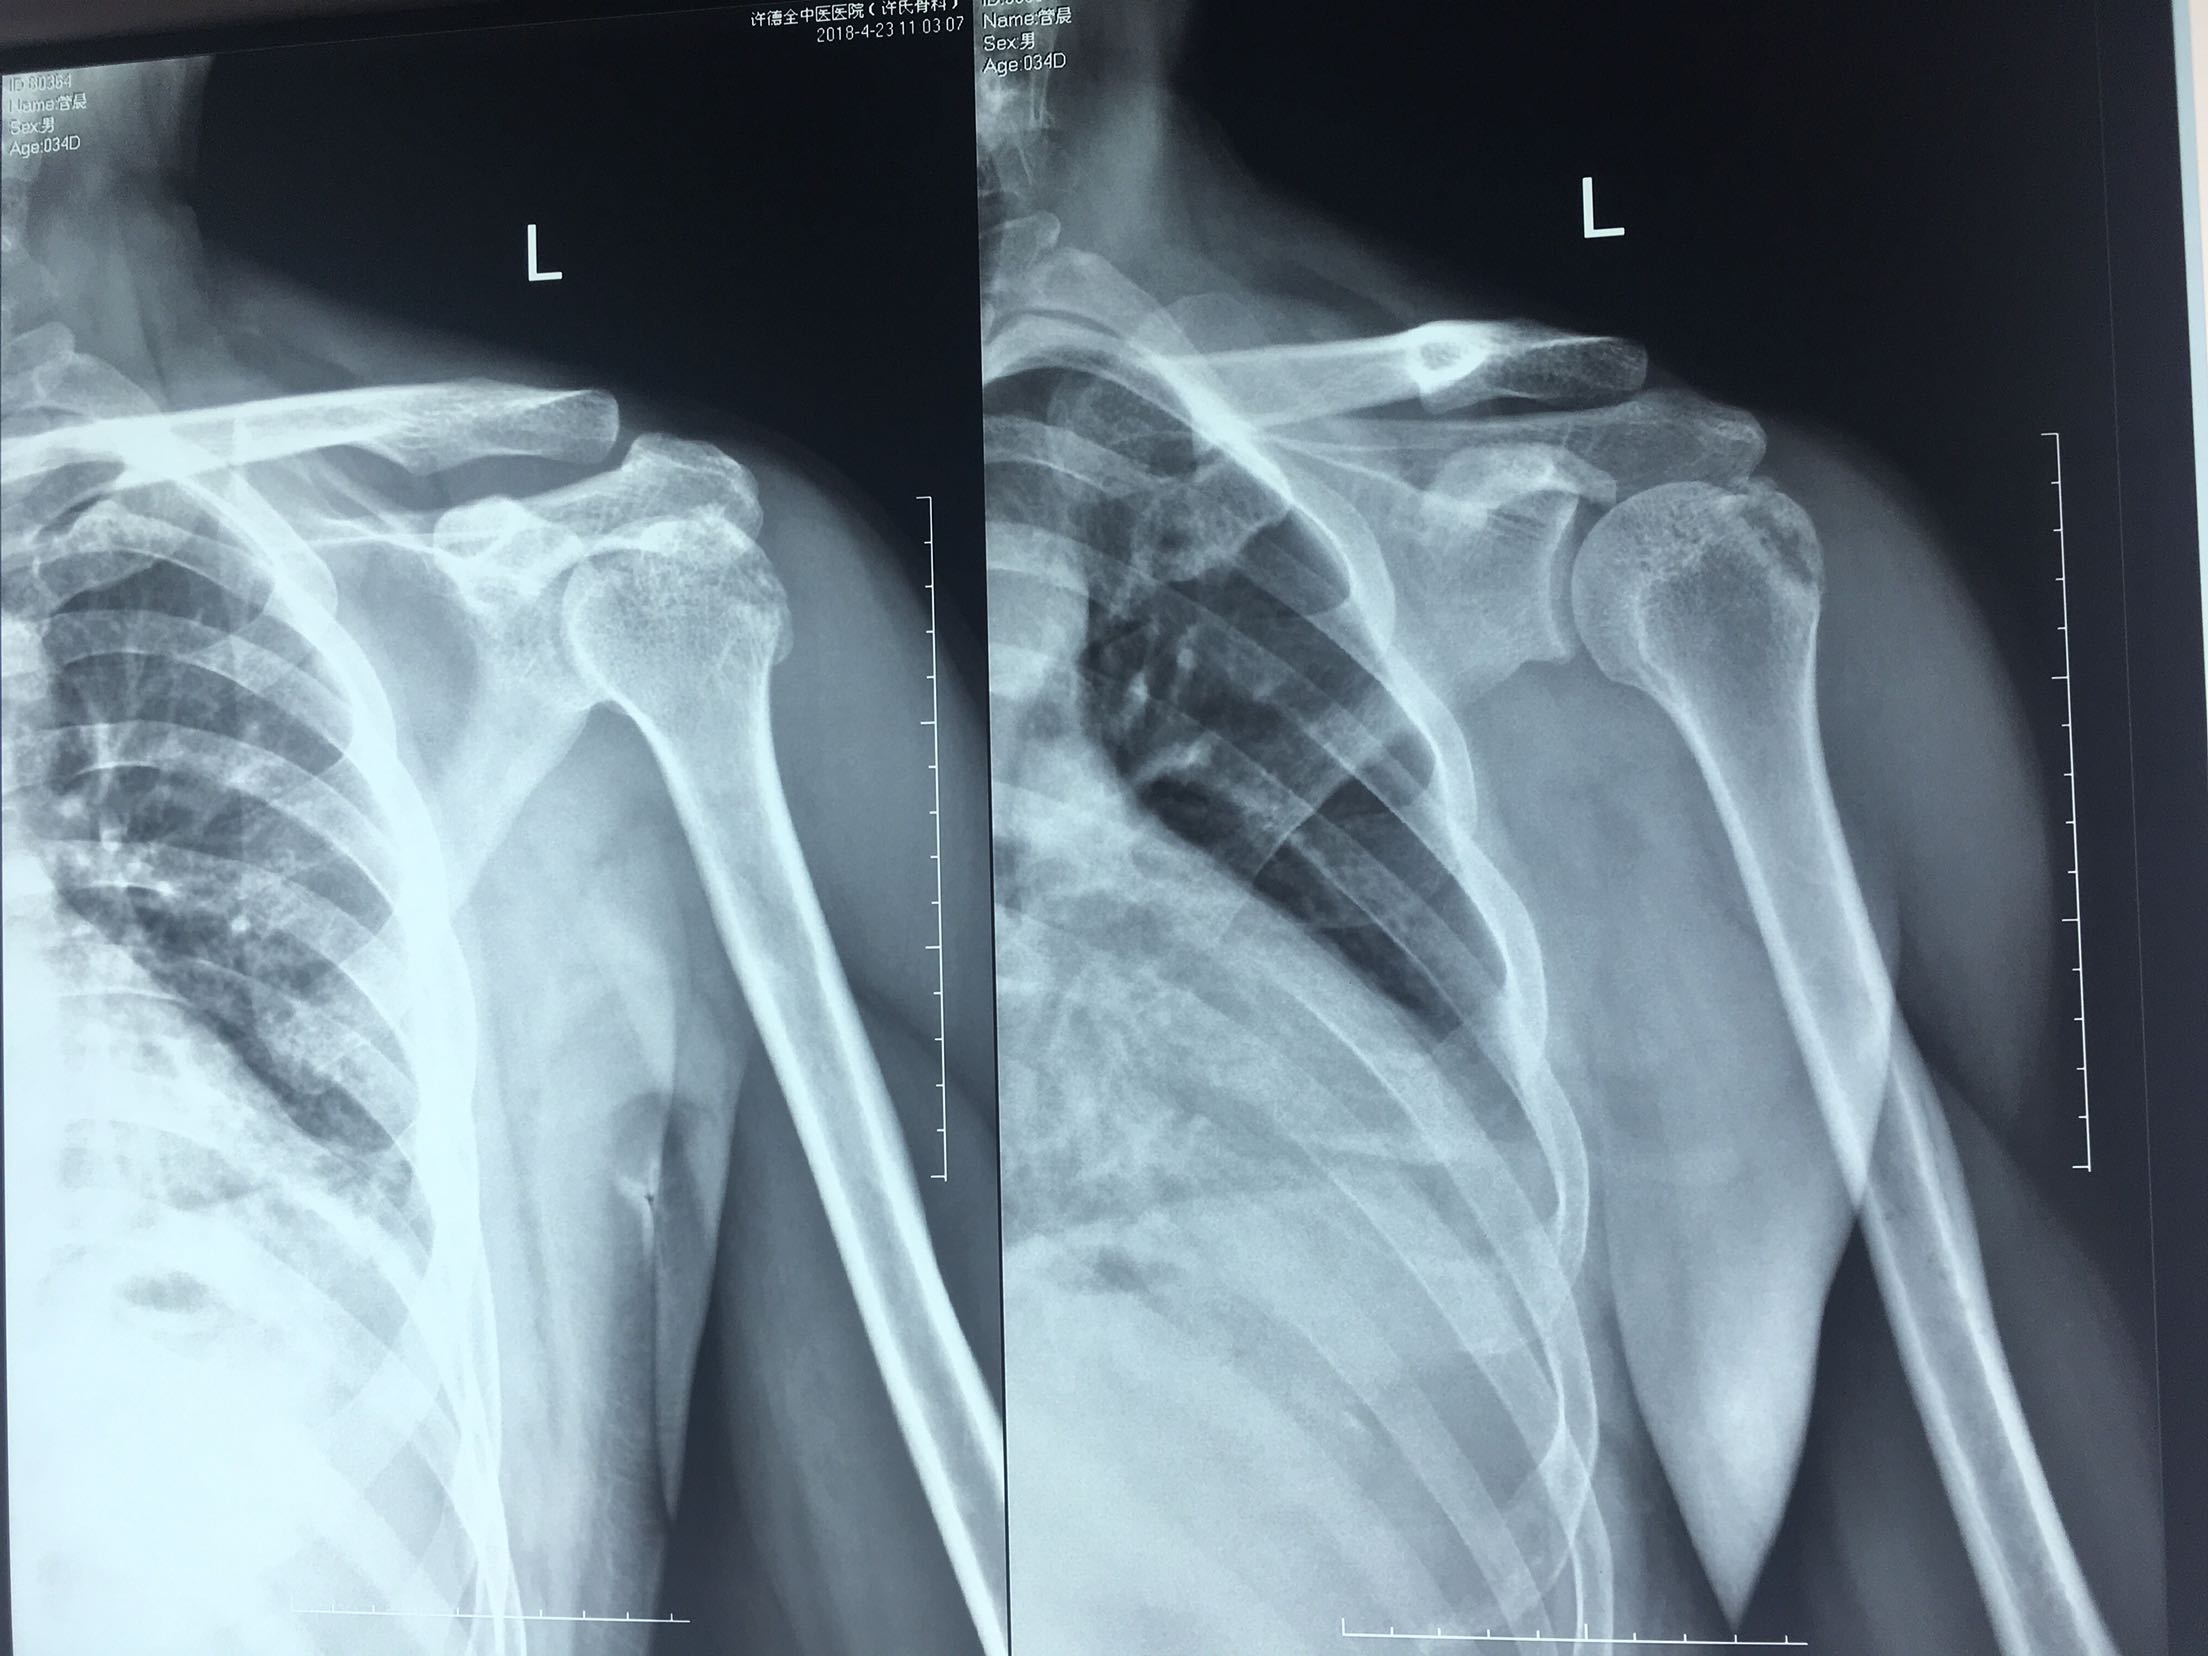

肩关节脱位并大结节骨折

肩关节脱位并骨折

右肩关节脱位并肱大结节撕脱性骨折